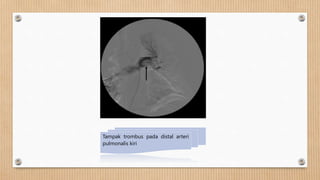

Tampak trombus pada distal arteri

pulmonalis kiri